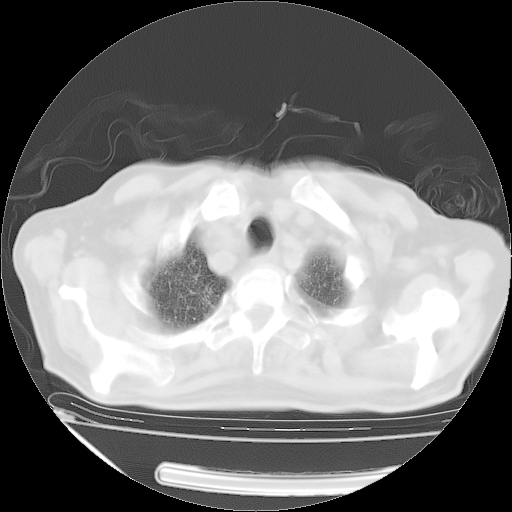

甲强龙80mg/日+抗结核治疗(异烟肼+利福霉素+乙胺丁醇)10天。复查肺部CT。

治疗10天肺部CT